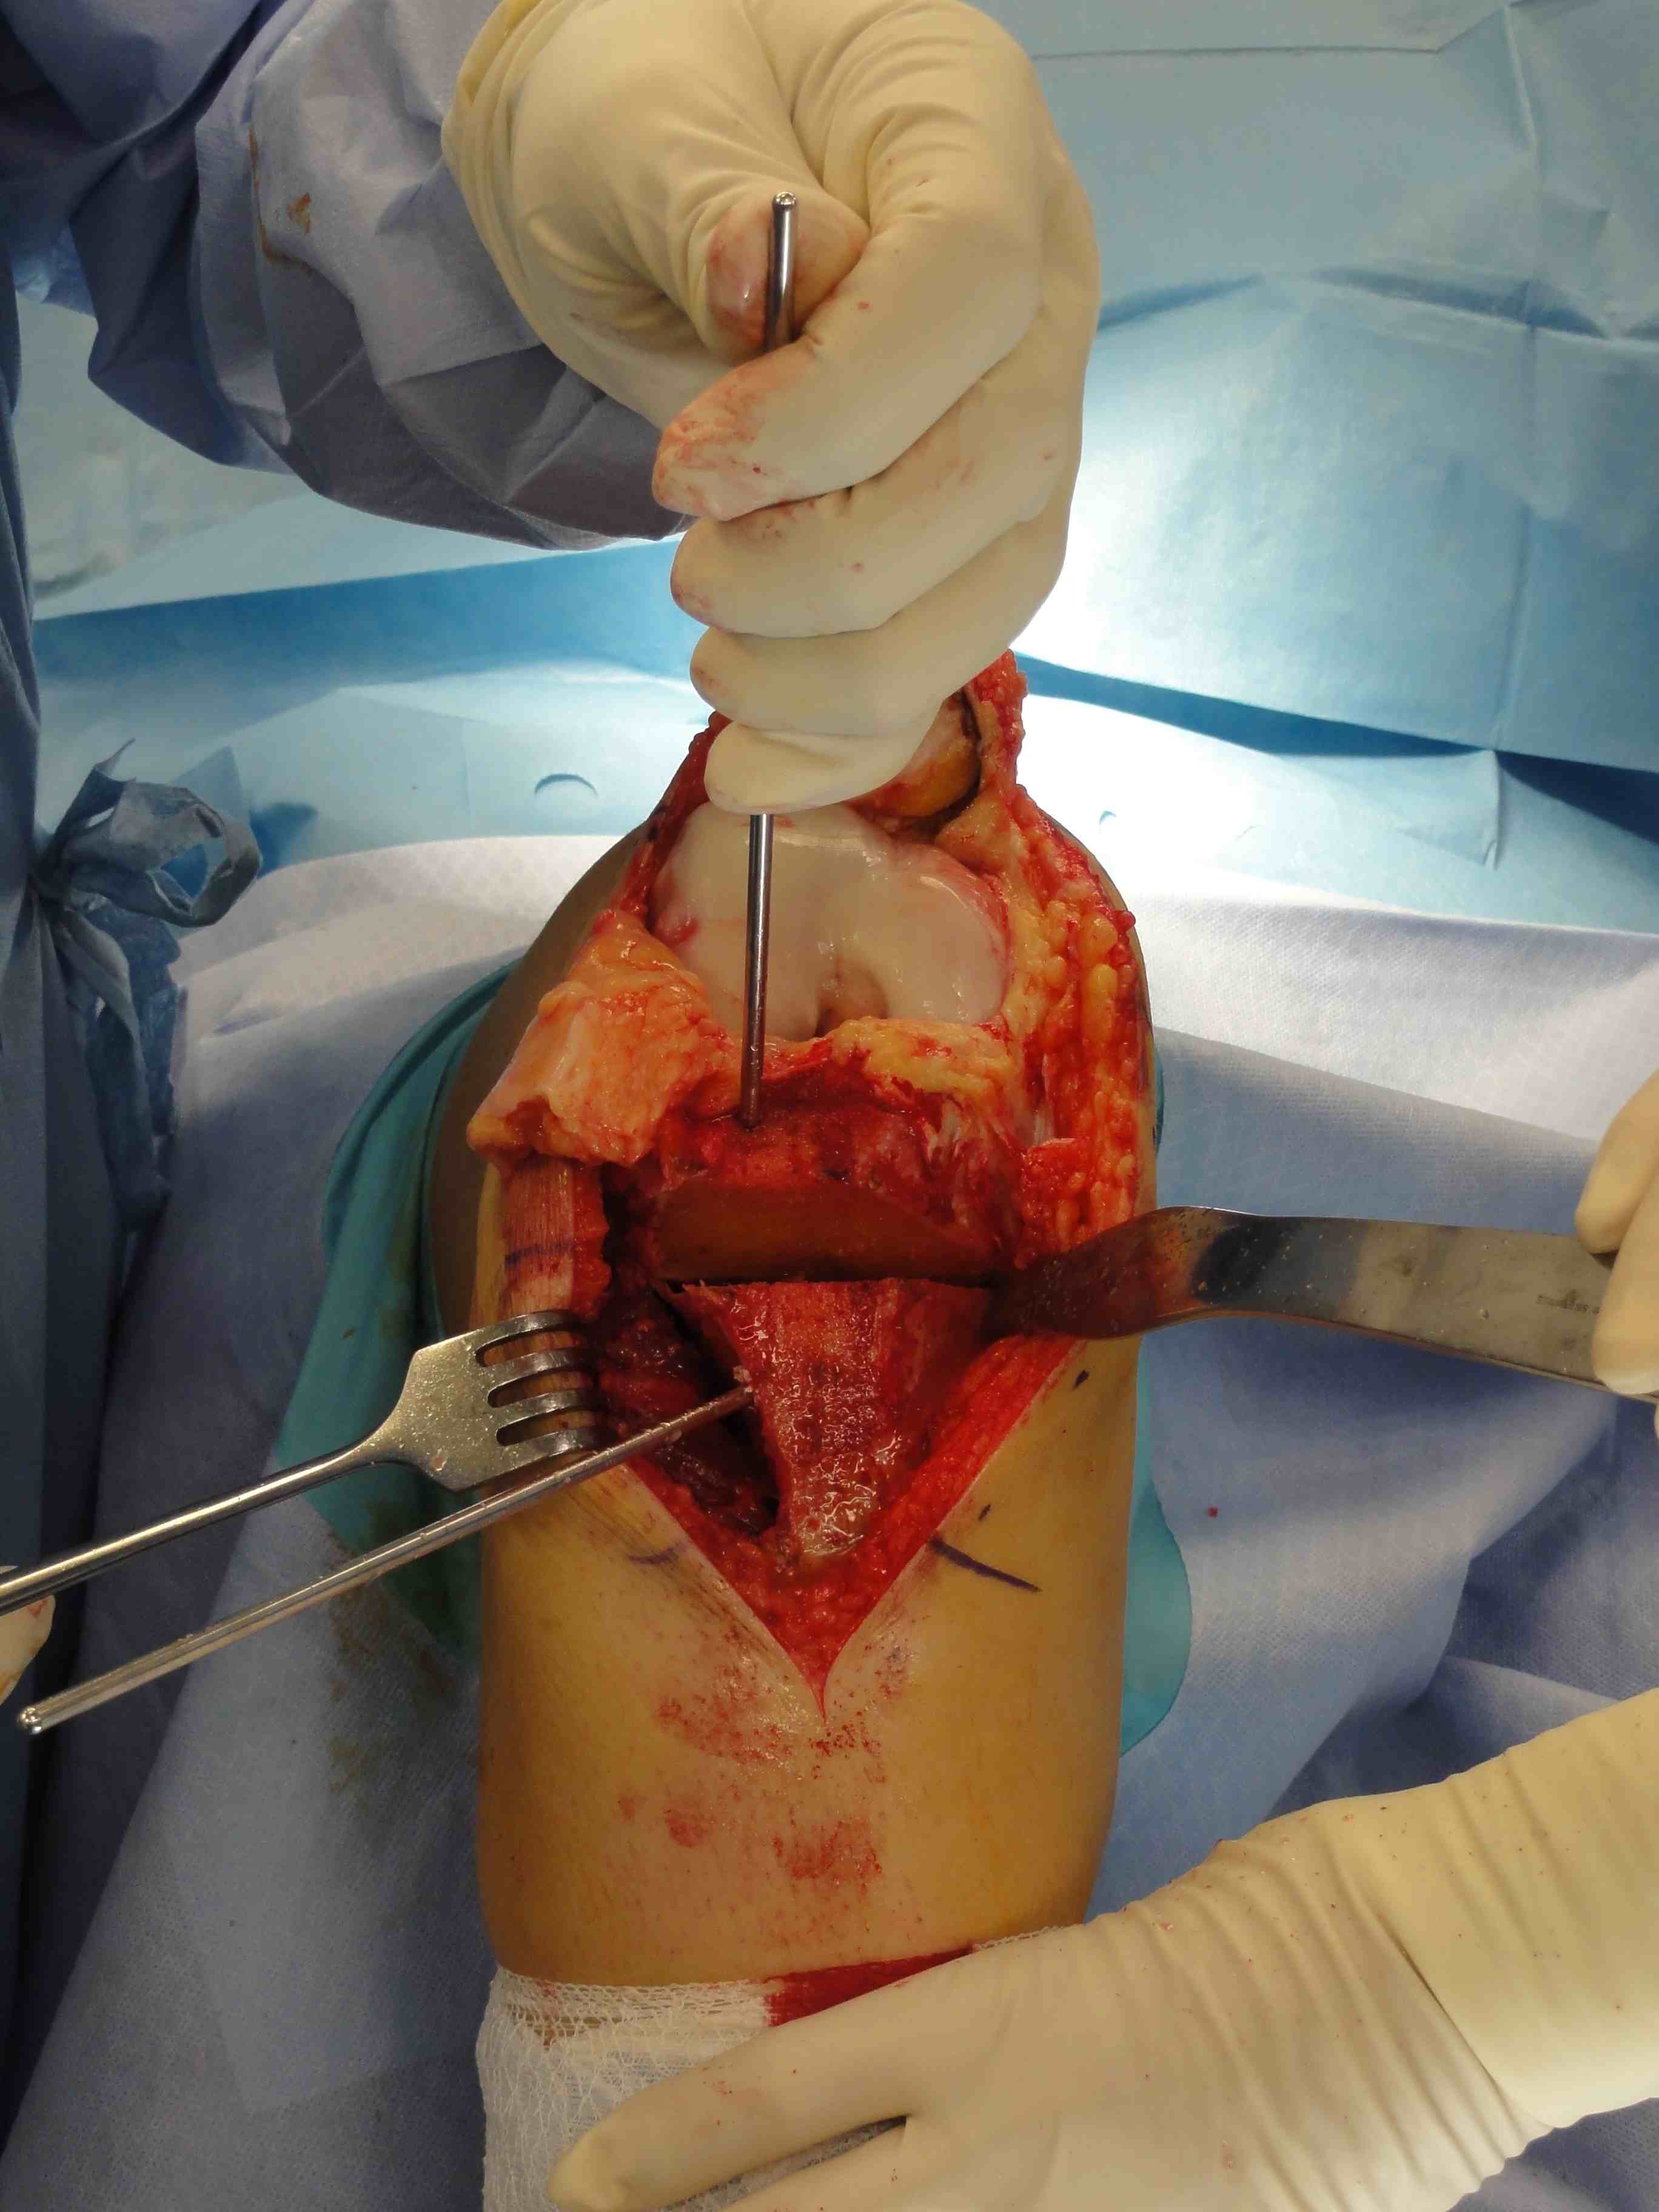

- medial incision

- beware overtightening (will give pain) / patella fracture (drill holes in patella)

- reassess for stability